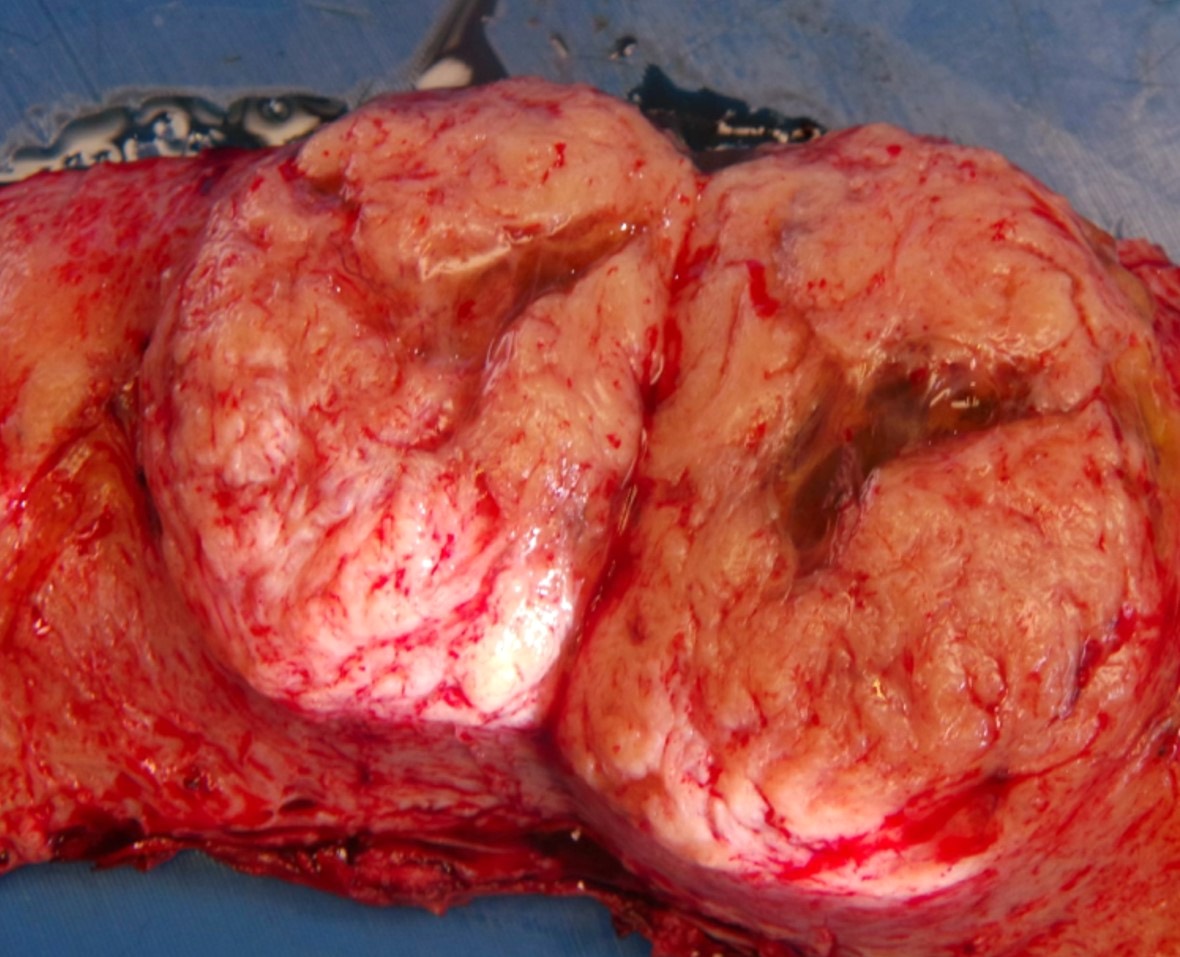

Gross description

- Typically well circumscribed but nonencapsulated

- On cut surface: white or tan-white, whorled, firm, bulging

- Hemorrhage and infarction can be present in large tumors

- Calcifications can be present

- Apoplectic change (foci of hemorrhage) associated with progesterone therapy

Gross images